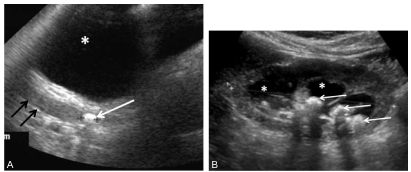

Fig. 27.1. Calculs en échographie.

Calcul dans le bas uretère rétrovésical (A, flèche blanche) avec dilatation de l’uretère pelvien (flèches noires) en arrière de la vessie (∗). Multiples calculs (B, flèches) avec cône d’ombre acoustique dans des cavités excrétrices dilatées (∗).

- l’échographie permet le diagnostic de dilatation des cavités rénales du côté de l’obstruction (qui peut manquer initialement ou être retardée de 12 à 24 heures) et de repérer le calcul urétéral, notamment à la jonction urétérovésicale (figure 27.1) ;

En échographie, tous les calculs, quelle que soit leur composition, se présentent sous la forme d’une image très échogène avec un cône d’ombre postérieur bien limité (cf. figure 27.1).